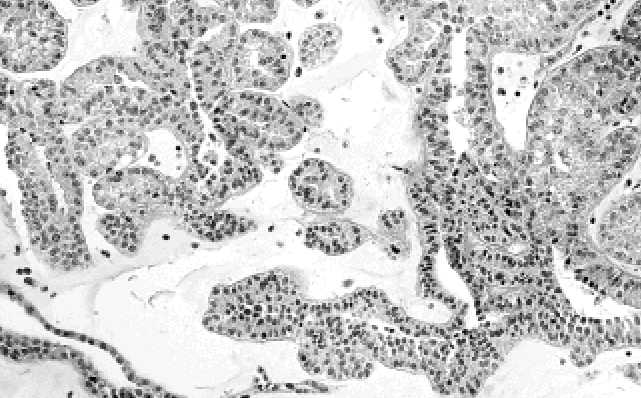

(Obr. C.3.1.). Dlouhé, větvící se tubulární struktury jsou též u metanefrického ade-

nomu časté (Obr. C.3.2.). Stroma je buďto nenápadné nebo je chudě buněčné a edé-

Obr. C.3.2. Dlouhé, větvící se tubulární struktury jsou též u metanefrického adenomu časté.